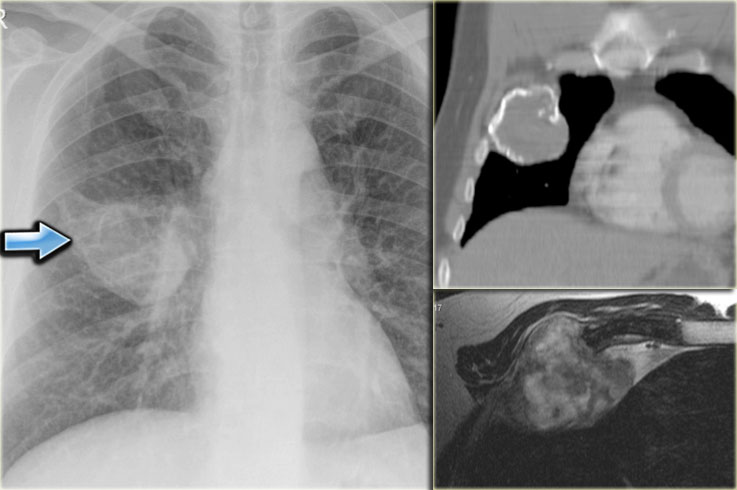

Chest X-ray shows non-specific soft tissue mass in the right lower lobe.

CT shows the mass extending from the posterior chest wall, with irregular calcifications, consistent with chondrosarcoma.

Diagnosis: high grade chondrosarcoma.